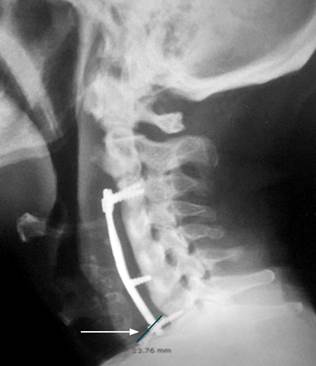

We report the case of a 60-year-old male with no significant comorbid conditions. The patient had a history of cervical trauma from a road traffic accident 12 years prior, which necessitated a C4-C5-C6 corpectomy and anterior cervical fixation using prosthetic material. Subsequently, the patient developed cervical myelopathy and symptomatic spinal stenosis. He sought medical advice for persistent dysphagia, weight loss, and dysphonia over six months. Neurosurgical evaluation led to the performance of a cervical spine radiograph, which revealed anterior displacement of the C7 fixation screw (Figure 1).